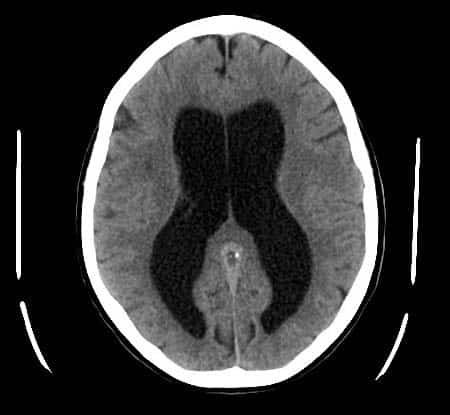

The ventricular system is a set of communicating cavities within the brain. These structures are responsible for the production, transport and removal of cerebrospinal fluid, which bathes the central nervous system. In this article, we shall look at the functions and production of cerebrospinal fluid, and the anatomy of the ventricles that contains it. Pro Feature - 3D Model You've Discovered a Pro Feature Access our 3D Model Library Explore, cut, dissect, annotate and manipulate our 3D models to visualise anatomy in a dynamic, interactive way. Learn More Functions of Cerebrospinal Fluid Cerebrospinal fluid is an ultrafiltrate of plasma that surrounds the brain and spinal cord. It serves three main functions: Protection – acts as a cushion for the brain, limiting neural damage in cranial injuries. Buoyancy – by being immersed in CSF, the net weight of the brain is reduced to approximately 25 grams. This prevents excessive pressure on the base of the brain. Chemical stability – the CSF creates an environment to allow for proper functioning of the brain, e.g. maintaining low extracellular K+ for synaptic transmission. By TeachMeSeries Ltd (2025) Fig 1Overview of the cerebrospinal fluid distribution in the brain Ventricles of the Brain The ventricles are structures that produce cerebrospinal fluid, and transport it around the cranial cavity. They are lined by ependymal cells, which form a structure called the choroid plexus. It is within the choroid plexus that CSF is produced. Embryologically, the ventricular system is derived from the lumen of the neural tube. In total, there are four ventricles – right and left lateral ventricles, third ventricle and fourth ventricle. Lateral Ventricles The left and right lateral ventricles are located within their respective hemispheres of the cerebrum. They have ‘horns’ which project into the frontal, occipital and temporal lobes. The volume of the lateral ventricles increases with age. By TeachMeSeries Ltd (2025) Fig 2Bird’s eye view of a cast of the ventricular system of the brain. Third Ventricle The lateral ventricles are connected to the third ventricle by the foramen of Monro. The third ventricle is situated in between the right and the left thalamus. The anterior surface of the ventricle contains two protrusions: Supra-optic recess – located above the optic chiasm. Infundibular recess – located above the optic stalk. Fourth Ventricle The fourth ventricle is the last in the system – it receives CSF from the third ventricle via the cerebral aqueduct. It lies within the brainstem, at the junction between the pons and medulla oblongata. From the 4th ventricle, the fluid drains into two places: Central spinal canal – bathes the spinal cord Subarachnoid cisterns – bathes the brain, between arachnoid mater and pia mater. Here the CSF is reabsorbed back into the circulation. By TeachMeSeries Ltd (2025) Fig 3The anatomical positioning of the ventricles of the brain. Production and Reabsorption of Cerebrospinal Fluid Cerebrospinal fluid is produced by the choroid plexus, located in the lining of the ventricles. It consists of capillaries and loose connective tissue, surrounded by cuboidal epithelial cells. Plasma is filtered from the blood by the epithelial cells to produce CSF. In this way, the exact chemical composition of the fluid can be controlled. Drainage of the CSF occurs in the subarachnoid cisterns (or space). Small projections of arachnoid mater (arachnoid granulations) protrude into the dura mater. They allow the fluid to drain into the dural venous sinuses. Learn more about the production and reabsorption of cerebrospinal fluid here. By TeachMeSeries Ltd (2025) Fig 4Coronal section of the skull, meninges and cerebrum. An arachnoid granulation is visible in the centre. Clinical Relevance Hydrocephalus Hydrocephalus is defined as an abnormal collection of cerebrospinal fluid within the ventricles of the brain. It is a serious condition, with chronic hydrocephalus causing raised intracranial pressure, and consequently cerebral atrophy. Based on the underlying cause, there are two clinical classifications: Communicating (Non-obstructive) Hydrocephalus – Abnormal collection of CSF in the absence of any flow obstruction in the ventricles. Common causes usually involve the functional impairment of the arachnoid granulations, such as fibrosis of the subarachnoid space following a haemorrhage. Non-communicating (Obstructive) Hydrocephalus – Abnormal collection of CSF, with flow obstructed within the ventricular system. The most common site of obstruction is the cerebral aqueduct, connecting the third and fourth ventricles. There is also a third classification, hydrocephalus ex vacuo – this refers to ventricular expansion, secondary to brain atrophy. This is often seen in patients with neurodegenerative conditions, such as Alzheimer’s disease. Treatment of hydrocephalus primarily involves reversing the cause. Whilst treating the cause, a shunt can be inserted, which drains the fluid into the right atrium or the peritoneum. By Lucien Monfils [CC-BY-SA-3.0-2.5-2.0-1.0], via Wikimedia Commons Fig 5Hydrocephalus on a CT scan. Do you think you’re ready? Take the quiz below Pro Feature - Quiz The Ventricles of the Brain Question 1 of 3 Submitting... Skip Next Rate question: You scored 0% Skipped: 0/3 1800 More Questions Available Upgrade to TeachMeAnatomy Pro Challenge yourself with over 1800 multiple-choice questions to reinforce learning Learn More Rate This Article